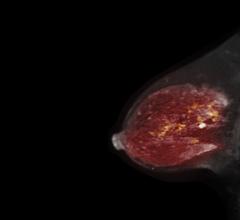

Despite decades of progress in breast imaging, one challenge continues to test even the most skilled radiologists ...

While most women understand the importance of health screenings, an estimated 72 million have missed or postponed a ...